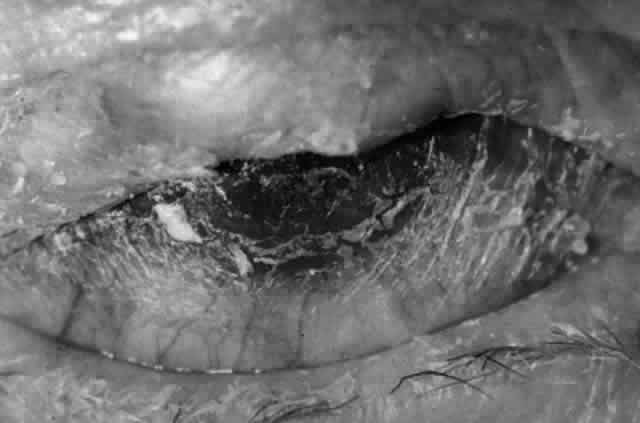

Clinically, the ocular disease in cicatricial pemphigoid (OCP) may present unilaterally in the form of a chronic, recurrent catarrhal conjunctivitis, but it eventually becomes bilateral. Subepithelial fibrosis is characteristic of stage 1 of OCP (Fig. 7). Stage 2 shows fornix foreshortening (Fig. 8), and symblepharon formation is the hallmark of stage 3 (Fig. 9). Stage 4, end-stage disease, is characterized by ankyloblepharon and surface keratinization (Fig. 10). Obstruction of the lacrimal ductules and meibomian gland ducts eventually produces an unstable tear film and progressive sicca syndrome, but it is to be emphasized that OCP is not a dry-eye syndrome until late in the disease course.20 Trichiasis and entropion occur because of the subepithelial fibrosis, with eventual keratopathy, corneal neovascularization, and corneal ulceration and scarring.20

Fig. 7. Stage 1 cicatricial pemphigoid, with cicatrizing conjunctivitis, and fine striae-type areas of subepithelial fibrosis, but without evidence of shrinkage of the conjunctiva.